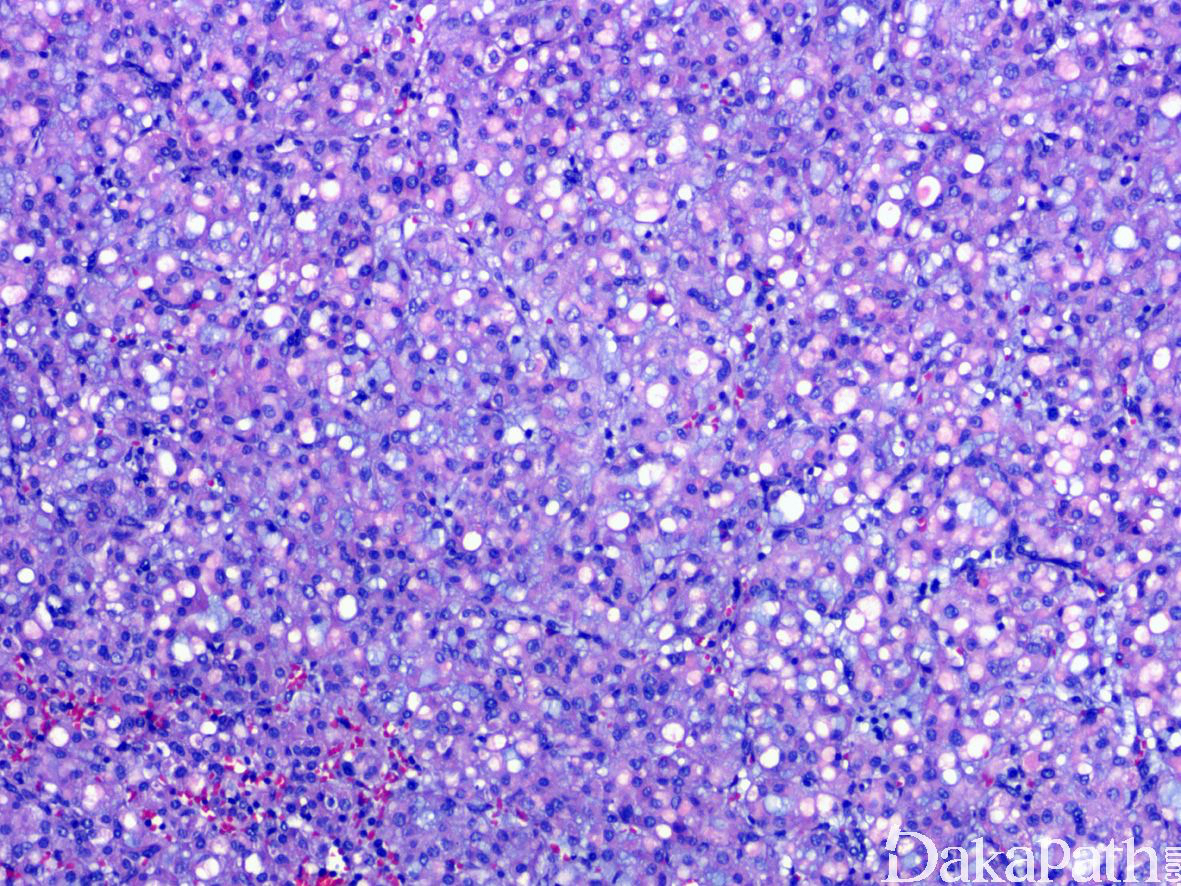

4,形态学上肿瘤一般界限较清楚部分带包膜,整体上呈分叶状或推挤状状生长,周边常见内陷的良性肾小管,常表现为不规则分支和乳头状结构。瘤细胞以实性、巢状排列为主,常见不同程度的微囊或多囊性扩张以及小管形成,偶尔可见乳头状生长结构。瘤细胞胞浆丰富,嗜酸性,SDH-RCC 最具特征性的组织学表现为胞浆内存在半透明的包涵体,内含嗜酸性或浅染的絮状物质,当这一改变显著时可造成肿瘤明显的空泡状低倍观。

5,肿瘤细胞核形态通常较温和,具有神经内分泌样的染色质,Fuhrman 核分级一般为 1 级或 2 级,偶尔可表现为高级别形态或肉瘤样转化。在高级别肿瘤中,SDH-RCC 特征性的胞浆内包涵体可能并不明显,需要广泛的取材仔细的寻找。肿瘤间质一般比较稀少,常见不同程度的水肿或出血,背景内可见较多量的肥大细胞浸润。